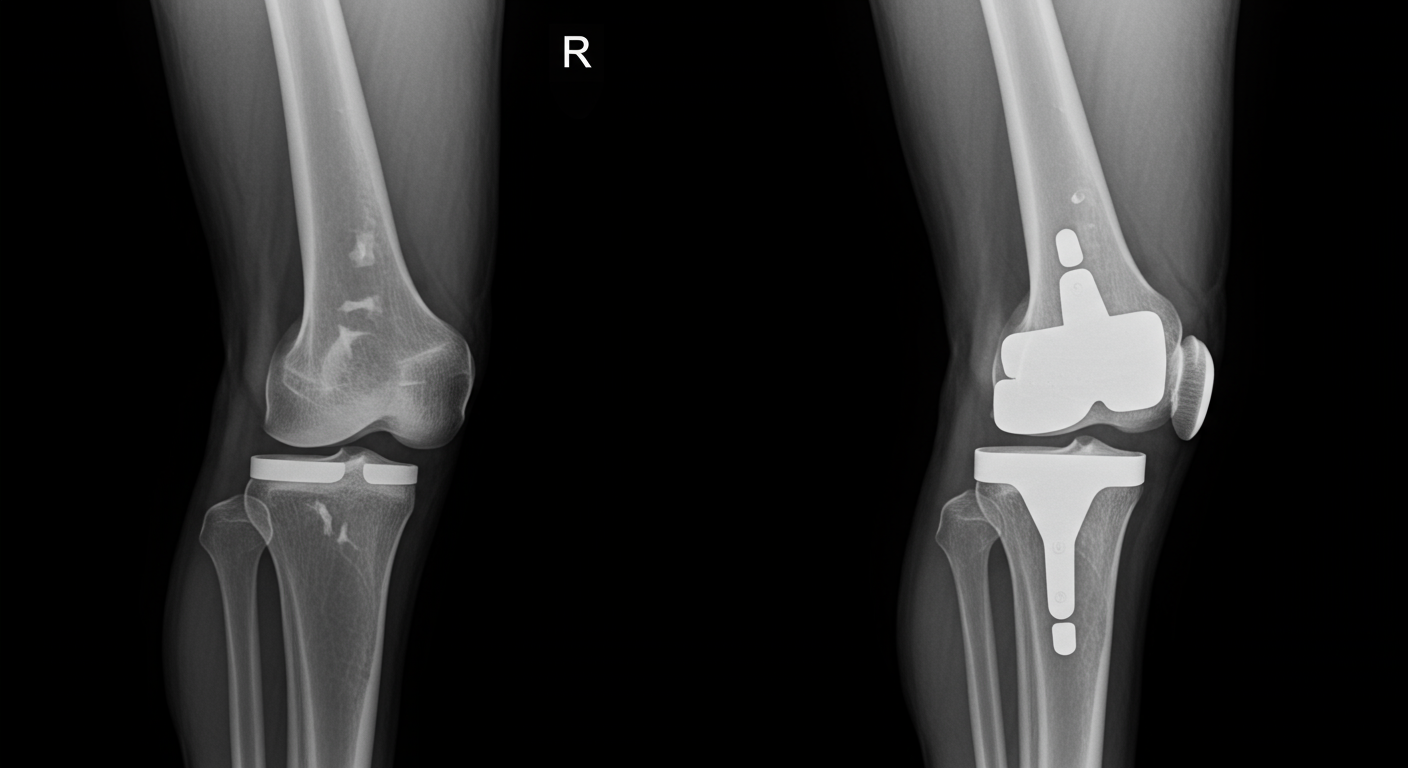

人工膝関節置換術(TKA:Total Knee Arthroplasty)は、膝関節の機能が著しく低下したり、強い痛みに悩まされている患者さんに対して行われる手術です。主に変形性膝関節症や関節リウマチなどが原因で行われることが多いんですよね。

2025年現在の人工膝関節置換術は、手術技術や人工関節の材質も大きく進化しています。耐久性が向上し、より自然な動きを実現する設計になっているため、手術後の満足度も高くなっているんですよ。一般的に人工関節の寿命は15〜20年程度とされていますが、最新の素材では更に長持ちする可能性があります。